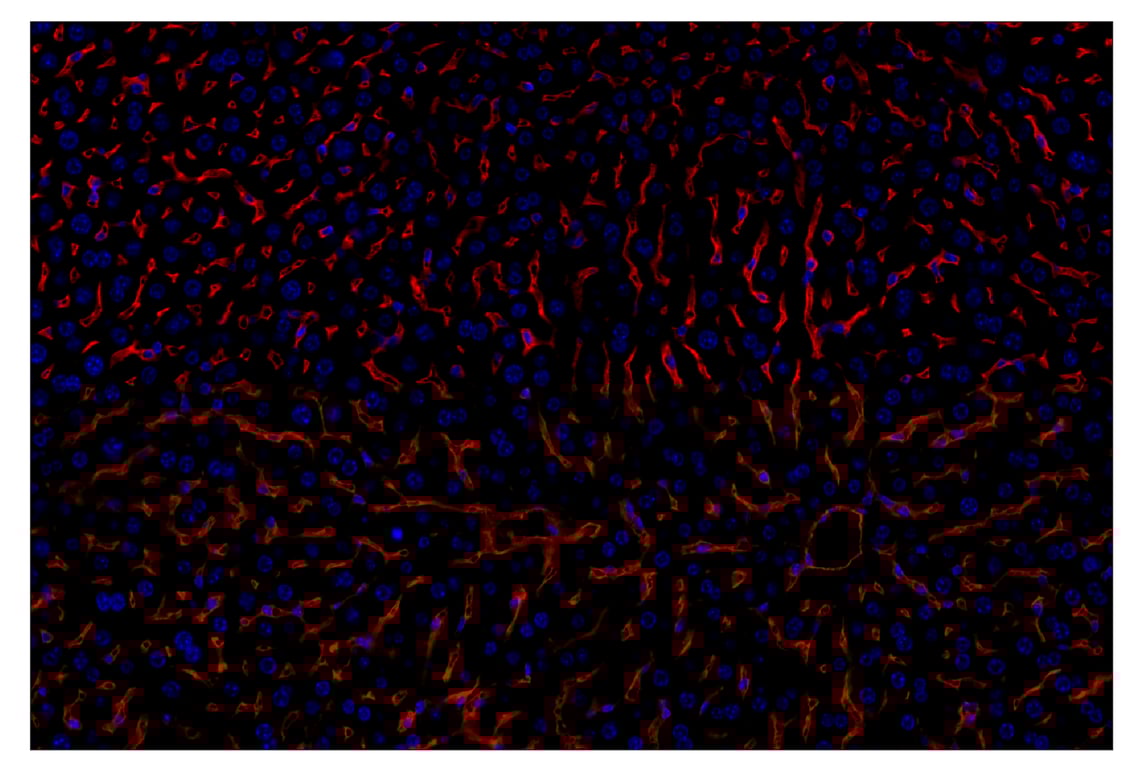

CD47 (E2V9V) Rabbit Monoclonal Antibody (Alexa Fluor® 647 Conjugate) #48456

Immunohistochemistry (Paraffin) 1:50

CD47 (E2V9V) Rabbit Monoclonal Antibody (Alexa Fluor® 647 Conjugate) recognizes endogenous levels of total CD47 protein.

Mouse